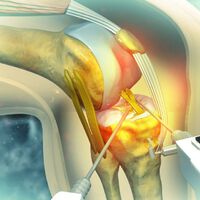

Fisioterapeuta: "a osteoartrite do joelho é um processo degenerativo natural e a dor pode ser causada por inflamação, inatividade ou outros fatores relacionados ao estilo de vida"

"Muitos pacientes chegam à clínica preocupados com a possibilidade de terem osteoartrite no joelho, convencidos de que sua articulação está 'desgastada' e que a única coisa a fazer é descansar ou se resignar à dor. Mas isso não é...